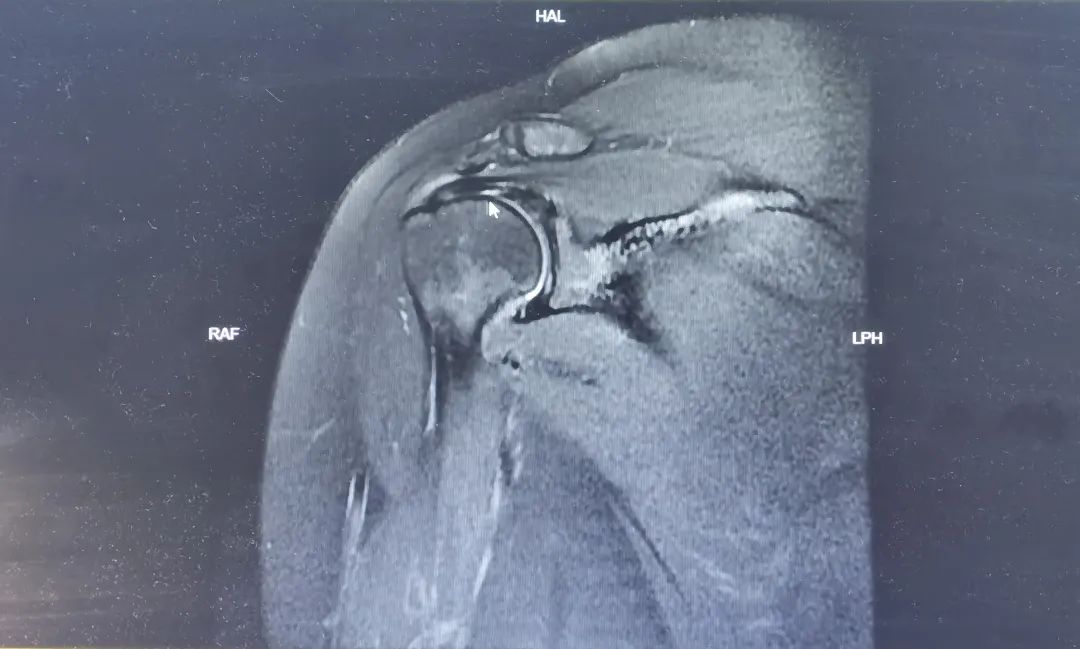

采用肌骨超声,能够清晰显示关节、肌肉、肌腱、韧带、周围神经、筋膜等软织结构及其发生的病变。超声引导下精准治疗可以清晰显示针尖位置、进针路径中的重要结构,明确将药物注入病变区域,解除病痛的同时能减少药物的使用量,也能避免伤周围血管、神经。

最后,骨科王主任特别提醒,出现肩关节疼痛切忌自行处理,在临床症状的肩痛中,超过60%的是肩袖损伤引起的,肩袖损伤不同于冻结肩,肩袖像橡皮筋一样存在回缩张力,已经撕裂的肩袖难以自愈,只有撕裂很小、症状较轻的患者可以暂时保守治疗,大部分患者需要通过肩关节镜完成微创修复手术。肩袖损伤如果被误诊为“肩周炎”可能延误治疗,小损伤进展为不可修复的肩袖损伤。建议居民朋友关注肩关节健康,专业求助及早干预,早日终结肩痛寒冬。